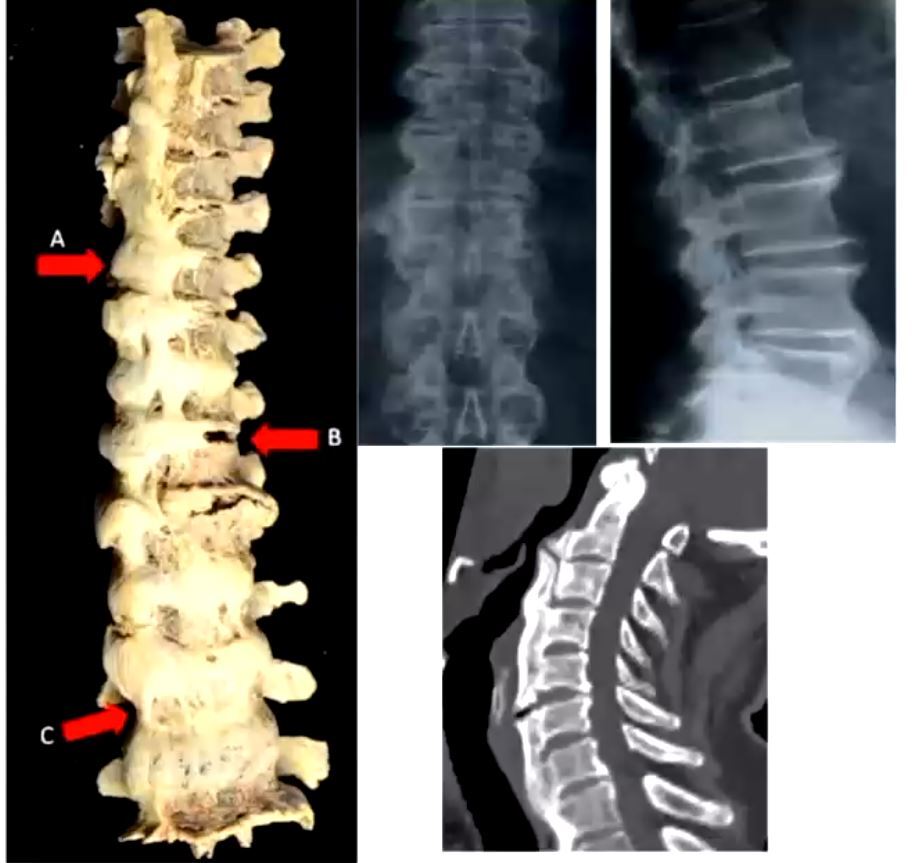

what is this condition, what causes it

diffuse idiopathic s h

lumpy ossification of anterior longditudinal lig